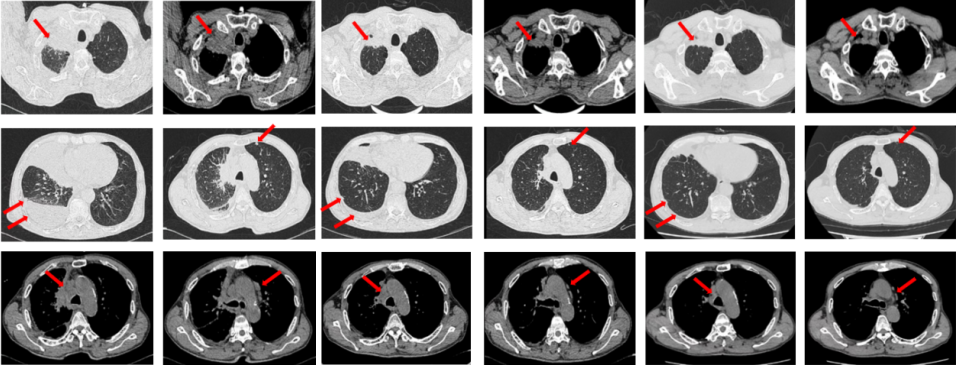

2022年7月至2022年11月行贝伐珠单抗联合培美曲塞/顺铂方案治疗6周期,2周期后评效PR,4周期后评效SD-(如图1)。第6周期治疗结束后患者自行终止治疗。

图1:由左至右分别展示基线(A.)及一线治疗后改变(B.和C.)。红色箭头指示病灶位置,由上至下分别为右肺肿物、右侧胸膜转移病灶及胸腔积液、左侧胸膜转移病灶、多发纵隔淋巴结肿大。